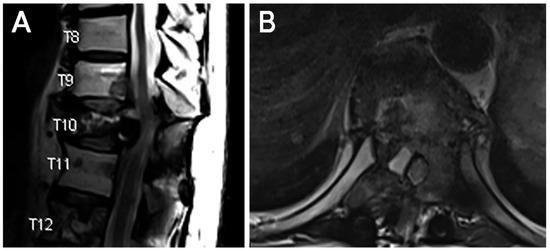

Using Endoscopic Approaches in the Surgical Management of Spinal Metastatic Disease

Patients with spinal metastasis often benefit from surgical intervention for debulking to improve neurologic deficits, reduce spinal cord or root compression, and ameliorate pain. Traditionally, large, open fusions have been used to achieve adequate decompression of neural structures. These types of interventions are frequently associated with significant blood loss, prolonged hospitalizations, and increased risk of surgery-related complications, which can delay postoperative chemotherapy and radiation therapies. Endoscopic spine approaches allow access to the spinal cord and nerve roots with minimal soft tissue disruption, which has been shown to reduce risks associated with open surgery in other contexts. Furthermore, the smaller incision, reduced blood loss, ability to position incisions away from radiation fields, and lower risk profile in high-risk patients may provide an effective solution to spinal metastases in appropriately selected cases. Here, we present two cases of spinal metastases successfully managed with spinal endoscopy and recommend the consideration of this approach for similar scenarios. Full article